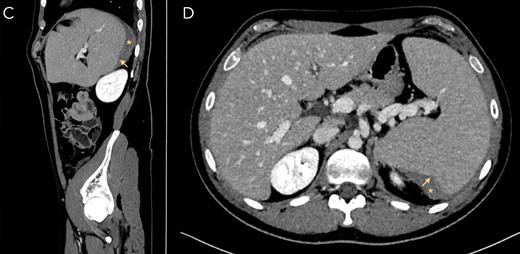

Computed tomography of splenic rupture

Yellow arrow indicates rupture site. Yellow asterisk marks subcapsular hematoma.